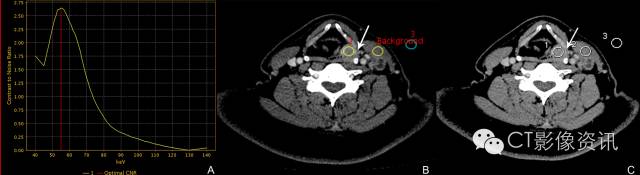

58岁男性 下咽癌患者,最佳CNR单能量55KeV是病变显示的最佳KeV。

69岁女性 下咽癌患者,转移淋巴结和病变走行及斜率基本一致,正常淋巴结与前两者有明显差异,提示是不同性质的组织。